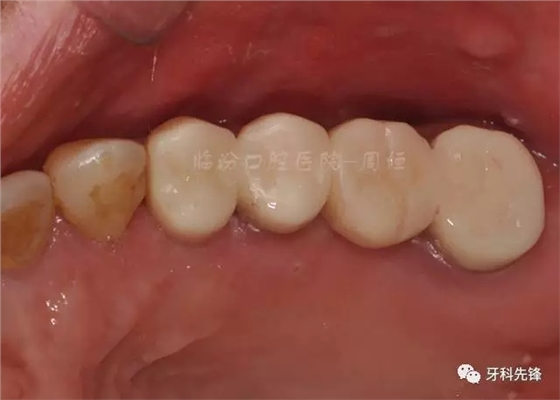

圖30術(shù)后頜面照

640.webp (34).jpg